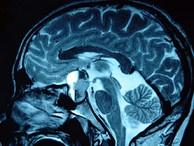

问题 男,47岁,头痛三年余,最近2个月感觉视力下降,MRI检查如图,最可能的诊断为()

选项 A.垂体瘤 B.颅咽管瘤 C.垂体囊肿 D.垂体腺瘤囊变 E.脑膜瘤

答案 D